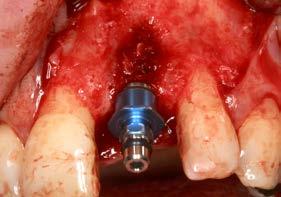

Se elevó un colgajo a espesor total con márgenes amplios (Figuras 4 y 5), lo que permitió recolectar hueso autógeno de las áreas adyacentes mediante un rascador óseo. Este abordaje facilitó además un cierre primario sin tensión tras la colocación del implante y la sobrecorrección. El hueso obtenido se mantuvo en PRGF-Endoret,

El lecho implantario se preparó mediante fresado biológico, ajustado al tipo de hueso y a las dimensiones del implante planificado. A continuación, se procedió a la inserción del implante, que alcanzó un torque de inserción adecuado, permitiendo dejarlo en fase de cicatrización con el pilar

correspondiente colocado. Una vez colocado el implante y el pilar de cicatrización, se realizó una técnica de sobrecorrección vestibular con el injerto particulado inmerso en PRGF-Endoret, recubriendo toda la zona con una membrana autóloga de fibrina (fracción 1 activada y retraída). Se suturó con monofilamento no reabsorbible, sin tensión, para evitar el colapso del volumen vestibular que se buscaba ganar (Figuras 7 a 10). Como provisional se empleó el propio diente de la paciente, ferulizado a los adyacentes con resina, a modo de puente Maryland (Figura 11).